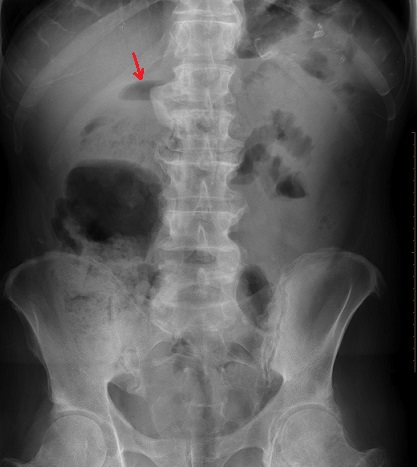

Image

radiologique ASP de pancreatite aigue est aspect de

niveau hydroaerique de sentinel ( sentinel loop ) (

fleche rouge ) |